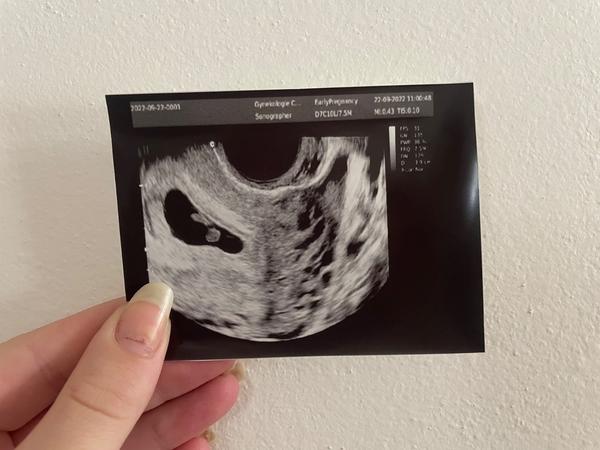

Šla mi udělat ultrazvuk a řekla “Ano tady to vidím” ale že prý tam není ani žloutkový váček ještě a že mám přijít za 2 týdny.

Ptala se mě jestli chci fotku, tak jí mám a když tak na ní koukám, tak mi přijde že tam jsou dvě komůrky. Ale ukázala mi jen tu jednu kde by mělo být to “miminko” ♥️ Označila jsem to šipkou.

Co myslíte mám plašit že tam jsou dvě mimi nebo jen jedno. Každopádně vím že je ještě brzy, ale nedokážu nad tím přestat přemýšlet.

@michajla1 Nejsem doktor, nevyznám se v ultrazvuku ale kdyby to byla moje fotka, tak si myslím, že jsou dvě😃❤️